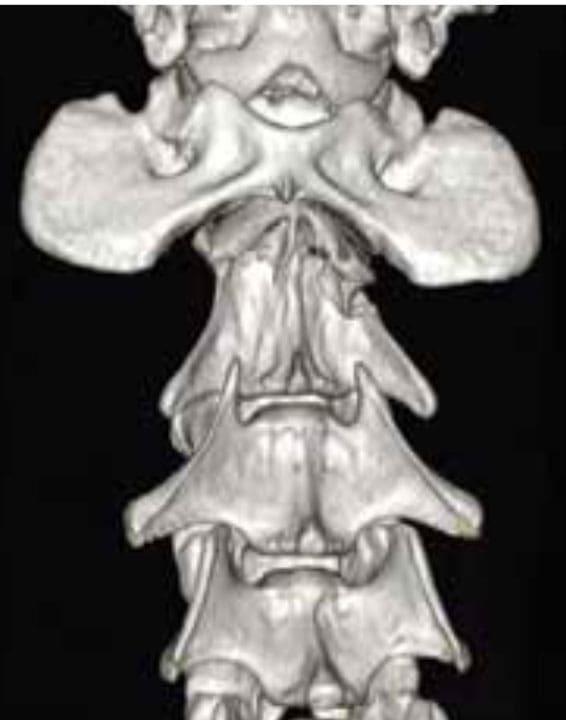

CT acquires axial ‘slices’ through the body and then using computer technology creates sagittal and coronal images. Therefore, CT loses a small amount of resolution in reconstruction of the two additional planes. CT images, however, can be rendered into a 3D animation, which is a very helpful tool for surgeon orientation, particularly for complicated fractures (see Figure 2). MRI acquires images in all three planes which overall means a higher resolution. However, MRI images cannot as easily be rendered into 3D animations.

Figure 2. A 3D rendering of C2 spinal fracture demonstrating fracture fragments, orientation and displacement, permitting accurate preoperative planning.